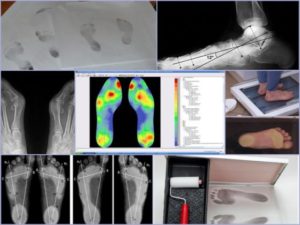

| Подометрия (плантография) | Измерение отпечатков стопы для оценки распределения нагрузки, выявления плоскостопия, определения типа свода стопы. | Диагностика плоскостопия, подбор ортопедических стелек, контроль эффективности лечения. |

| Рентгенография | Получение изображений костных структур стопы для выявления переломов, вывихов, артроза, остеомиелита, деформаций. | Травмы, боли в костях, подозрение на дегенеративные изменения, планирование операций. |

| Подоскопия (компьютерная плантография) | Динамическая оценка распределения давления на стопу при ходьбе и стоянии, выявление зон перегрузки. | Подбор ортопедических стелек, оценка походки, контроль эффективности лечения. |

Актуальный диагностический метод, позволяющий определить степень плоскостопия – это метод подометрии (методика Фринлянда), при котором вычисляется подометрический индекс. Обследование стопы заключается в измерении длины и высоты стопы, после чего показатель высоты нужно умножить на сто и разделить на показатель длины стопы. Норма от 29 до 31.

При плоскостопии обязательно назначается рентгенодиагностика. Снимок делается в положении стоя, чтобы создать нагрузку на стопы. С помощью рентген-снимка определяется состояние костей, суставов, можно исключить артрозы и другие заболевания суставов. Также по снимку изучаются углы деформации.

Что такое компьютерная плантография стоп: показания и техника проведения

Компьютерная диагностика стопы представляет собой уникальный метод обследования, предназначенный для выявления плоскостопия у пациентов. Эта методика помогает подтвердить или опровергнуть наличие патологий в области стопы. Исследование доступно как для детей, так и для взрослых.

Компьютерная плантография — новшество в медицине. Тест определения плоскостопия по одному отпечатку ног имеет множество вариаций. Компьютерная томография стала усовершенствованным, точным, современным исследованием стоп.

Слово “плантография” переводится с латыни, как planta (подошва ступни) и graphio (рисунок). Методика проведения плантографии отличается от других обследований простотой, информативностью, безопасностью.

Необычный способ диагностики позволяет изучить состояние ступни, изменения ее строения, опорную способность ног, другие отклонения от нормы.

Диагностика проводится классическим и компьютерным методом.

Первая методика заключается в следующих действиях:

- процедура проводится в спокойных условиях;

- на ступни больного наносятся красящие жидкости;

- пациент становится на белую плотную бумагу;

- сходит с листа;

- доктор оценивает образовавшийся отпечатки.

Старый проверенный метод можно провести в домашних условиях с помощью воды. Достаточно намочить ступни и стать на плотную бумагу. Потом обвести отпечаток карандашом. Результаты оцениваются визуально. Нормой считается, когда узкая часть подошвы занимает 1⁄3 этой линии. Паниковать стоит начинать, если след доходит до срединной линии стопы. Результат свидетельствует о наличии заболевания.

Существует современная технология, которая с помощью программы проверяет дефекты стопы. Техника проводит точные математические вычисления. Метод позволяет оценить сразу несколько параметров, отражающих состояние опорно-двигательной системы. Существует оптическая плантография.

Как проводится компьютерная плантография

Алгоритм выполнения компьютерной томографии включает несколько ключевых этапов:

- В начале процедуры врач обязан провести инструктаж по технике безопасности;

- Затем специалист вводит информацию о пациенте в компьютерную систему (ФИО, возраст, дата рождения, рост, вес);

- Пациент становится босыми ногами на специальную платформу, напоминающую стекло. В этом процессе происходит сканирование стоп. Неправильное положение тела может привести к искажению изображения. Для получения точных данных пациенту необходимо равномерно распределить вес на ноги. Соблюдение всех рекомендаций врача позволяет добиться высококачественных результатов;

- Для более полной оценки состояния здоровья врачи могут назначить обследование в различных плоскостях. Пациента просят сесть на стул, после чего сканируются ноги в сидячем положении;

- Компьютер выполняет анализ и обработку собранных данных;

- Врач изучает полученные результаты и формирует заключение о состоянии здоровья пациента.